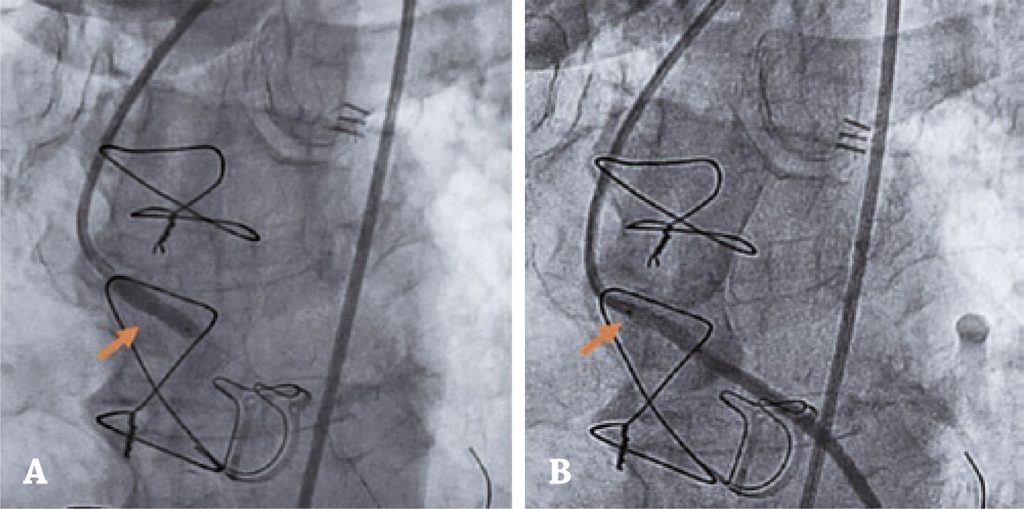

A substituição cirúrgica da válvula aórtica é o padrão-ouro para o tratamento da estenose aórtica sintomática grave. Complicações diretamente relacionadas ao procedimento cirúrgico são relativamente pouco frequentes. A estenose ostial da artéria coronária é uma complicação rara, mas potencialmente fatal, cujo exato mecanismo patogênico é desconhecido, embora algumas hipóteses já tenham sido propostas. Apresentamos um caso de síndrome coronariana aguda recorrente nos primeiros 12 meses após substituição cirúrgica da válvula aórtica realizada simultaneamente com cirurgia de revascularização do miocárdio, resultante da estenose ostial coronariana bilateral por válvula aórtica protética. Quando houver suspeita dessa complicação, principalmente em pacientes instáveis, a pronta confirmação diagnóstica e a revascularização precoce são cruciais. Nesse cenário clínico, a intervenção coronária percutânea foi considerada a melhor opção de revascularização.